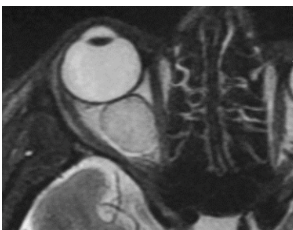

Clave en imagen para dx de retinoblastoma

Calcificaciones intraoculares

Q

A

Calcificación “manchada” o punteada

Capta contraste

masa con densidad intermedia

Que evalúa la RM en retinoblastoma

evalúa implicaciones intra y extraoculares asi como intracraneales- Identificación de hemorragia retinal y rompe paredes